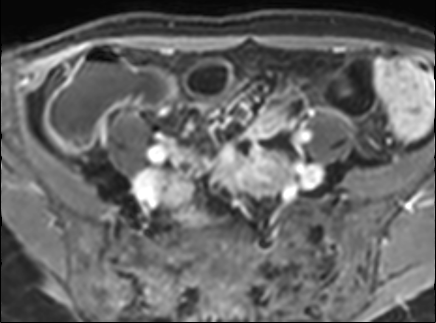

Bệnh nhân nữ 48 tuổi, đang điều trị bằng thuốc kháng TNF, được chỉ định nội soi đại tràng.

Phát hiện hẹp lòng ruột ở đại tràng sigma, không thể vượt qua được khi nội soi.

MR-enterography được thực hiện để đánh giá mức độ lan rộng của chỗ hẹp.

Ruột non bình thường, nhưng ghi nhận các đoạn hẹp ở đại tràng xuống và đại tràng ngang.

Cả hai đoạn hẹp đều có thành ruột dày đến 8 mm và ngấm thuốc rõ rệt theo kiểu niêm mạc ở đại tràng xuống và kiểu phân lớp ở đại tràng ngang.

Giãn ruột trước chỗ hẹp được ghi nhận ở cả hai đoạn.

Do các chỗ hẹp này không hiện diện khi nội soi đại tràng trước khi điều trị kháng TNF, nhiều khả năng chúng đã hình thành trong quá trình điều trị.

Do đó, quyết định phẫu thuật cắt đại tràng gần toàn bộ với miệng nối hồi-sigma đã được đưa ra.